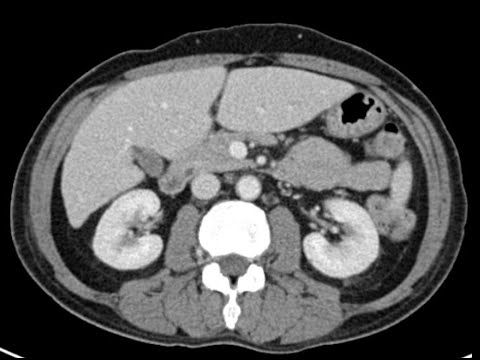

Textbooks can't teach you how to read a scan. This channel bridges the gap between theory and practice. I'm Rajesh, a radiologist in Toronto. I created this channel to give you the practical, real-world radiology training I wish I had as a resident. My videos are the antidote to the overwhelm from bloated textbooks and abstract lectures. They will help you: 1. Learn systematic, practical approaches to complex studies like CT and MRI. 2. Understand foundational concepts taught simply, from first principles. 3. Master the high-yield anatomy and pearls that matter in real-life practice. 4. Build the confidence to avoid simple mistakes and feel ready for your next shift. But watching videos isn't enough. You can only truly learn radiology through practice. That’s why we built the platform on NavigatingRadiology.com -- an interactive system with a full screen PACS viewer, curated high-yield courses, and an “AI Attending” that gives you instant feedback and guidance. Try it today!